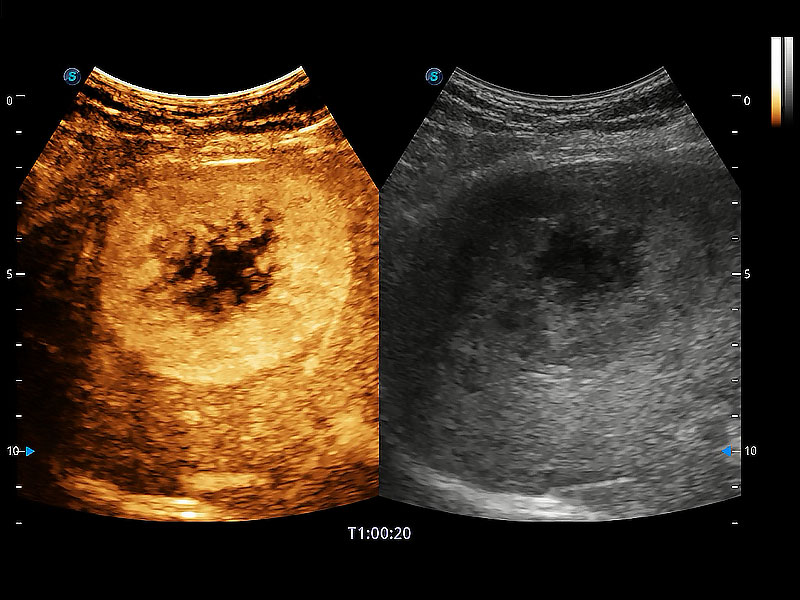

非线性融合造影成像充分利用谐波和基波信号,为难以观察的血流进行增强显像。可用于线阵、凸阵、微凸阵、相控阵探头。

能够增加心肌组织与血流之间的区别。对于心脏扫查困难的动物,可提供更好的心内膜边界的显示。

能够基于左心室壁追踪和辛普森法,自动计算射血分数,支持多个可移动点描迹,与手动测量相比,极大节省了动物医生的时间和精力。